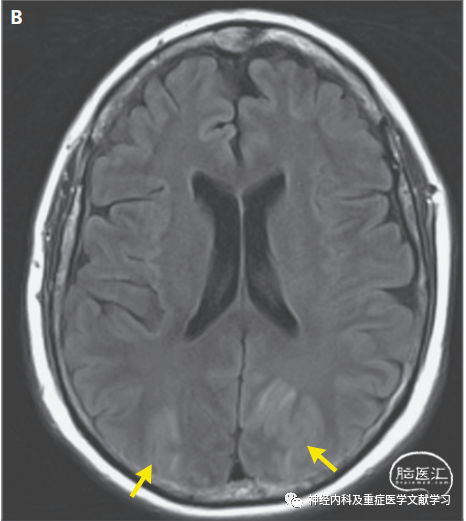

图2 双侧大脑半球分水岭区域PRES患者的影像学改变。

一名有卒中病史的63岁女性,以新发癫痫发作和精神状态下降为主诉入院。图A中患者轴向颅脑MRI FLAIR序列显示双侧大脑半球分水岭区域脑白质高信号(箭头)。图B中轴向磁敏感加权图像显示a图所示受累区域内有一小块出血区域(黄色箭头)。红色箭头表示顶叶内侧区域既往卒中引起的脑软化灶,但这一发现与PRES无关。